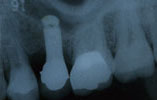

CASE6

上の歯全部がない場合 機能的回復

正面観

噛合面観

レントゲン

術前

術後

2本のインプラントを植立し、アタッチメント(磁石)を維持装置として、義歯を装着しました。

食事中にはずれることもなく、また義歯の上あごの部分をなくすことによって、食事時の違和感がなくなりました。